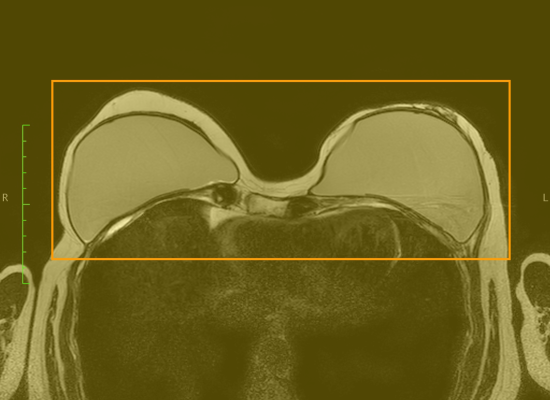

006 Fettsättigung bei Mammo-MRT